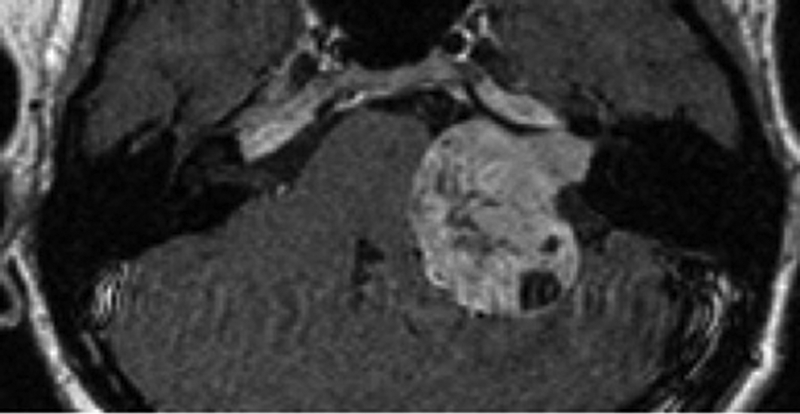

Imaging tinnitus

Tinnitus is a common sensation with a reported prevalence of 7-32%. The British National Study of Hearing recorded that 10% of adults suffered from prolong spontaneous tinnitus, and approximately a quarter of these are subsequently referred to hospital for investigation...